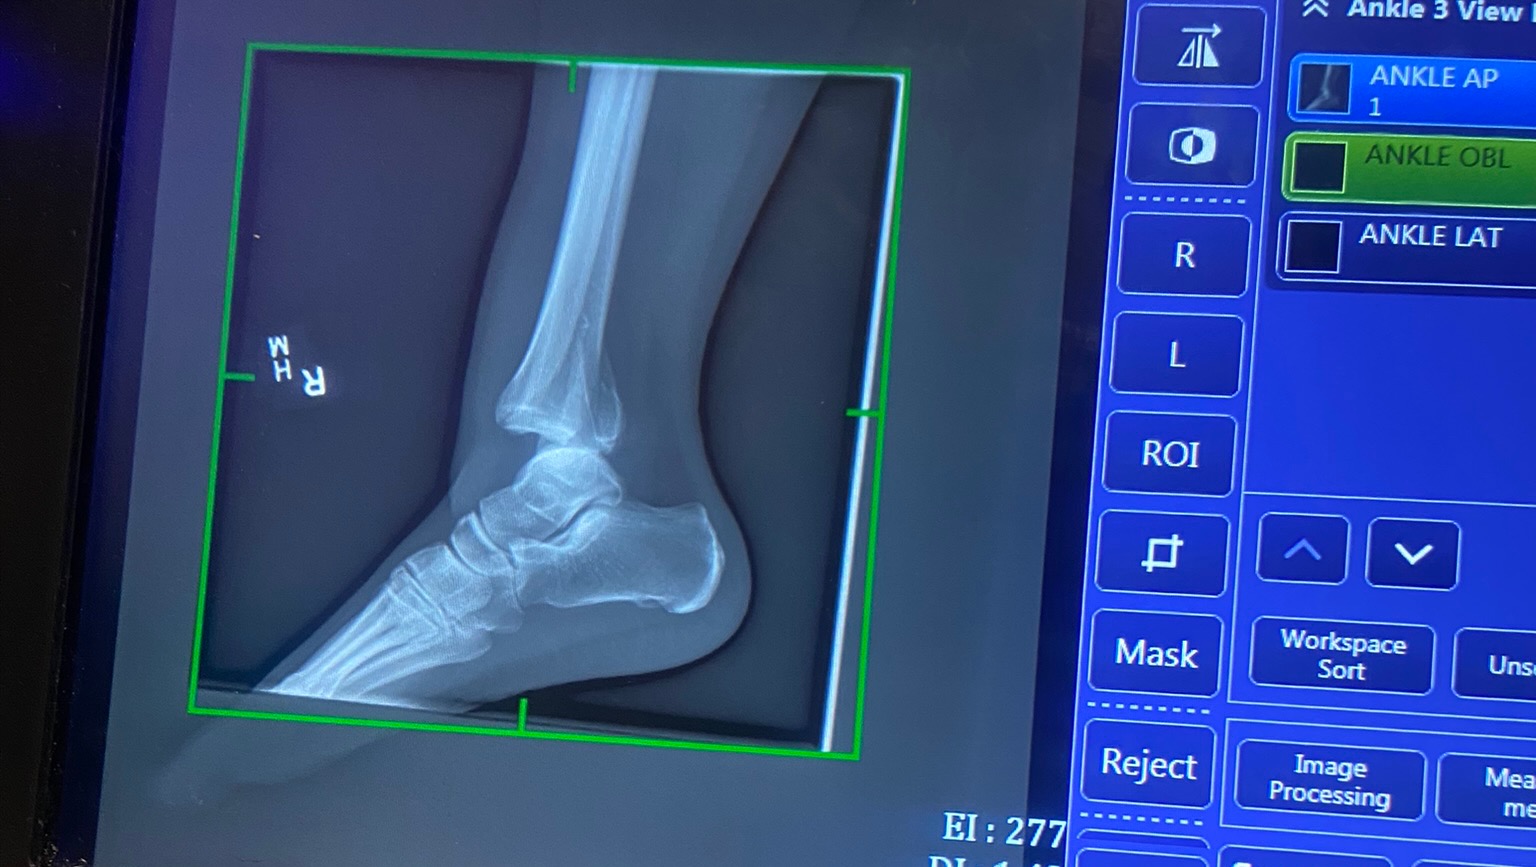

After a night in the emergency room we found out she has a trimalleolar fracture.

Which includes her fibula, tibia, and talus.

So technically all the bones that give your ankle and lower leg mobility.

She also has a severe ligament tear, and nerve damage on the top of her foot.

She will be having surgery tomorrow (4-18-23)